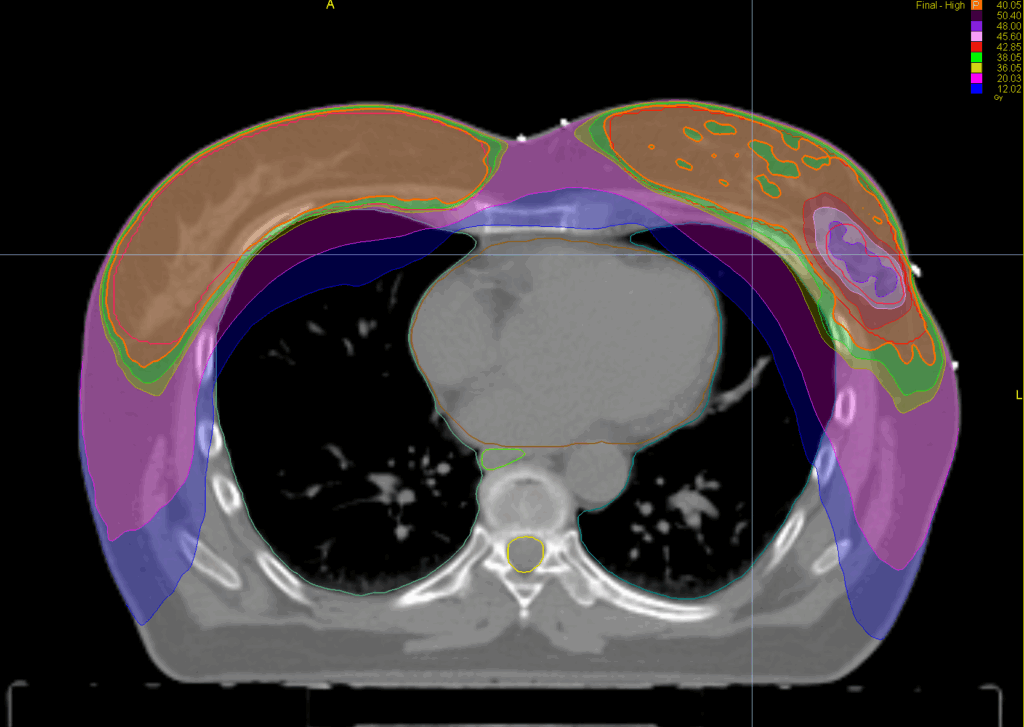

Treatment Plan Images

Fractionation / Protocol Used

40 Gy in 15 fractions

48 Gy (boost)

PTV(s) Volume, Length

1590 cc, 24 cm